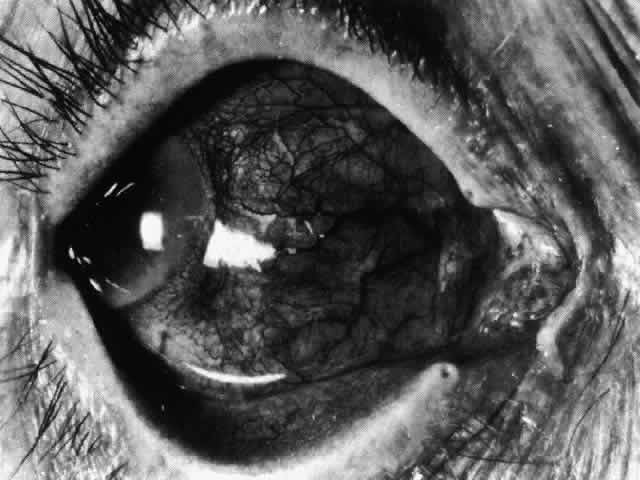

The sclera that is edematous is pushed forward, and the deep episcleral network is more congested than the superficial networks (Figs. 27 and 28). It is usually easy to ascertain by simple observation that the patient has scleritis and not episcleritis. However, it is not as easy to ascertain whether the patient has early necrotizing scleritis. It is in these patients that fluorescein angiography has considerable value, because the first changes are detectable in the ocular vasculature. Prompt and adequate treatment can prevent these changes from becoming irreversible.

Fig. 27. In scleritis, maximum congestion occurs in deep episcleral plexus, which is bowed forward by underlying scleral edema. Episcleral tissue is slightly infiltrated and superficial plexus is slightly congested (see Fig. 14). (Watson PG, Hayreh S, Awdry P: Episcleritis and scleritis. Br J Ophthalmol 52:278–279, 1968)

Diffuse Anterior Scleritis

Diffuse anterior scleritis is the most common and least severe type of scleritis. The inflammation is widespread, and it may involve either a small segment or the whole of the anterior segment, sometimes with such severe overlying inflammation as to justify the name “brawny” scleritis (Fig. 29). On slit lamp examination, the vascular pattern of both deep and superficial layers may be distorted, so that the normal radial pattern of the vessels is lost; large anastomotic channels develop, leading to beading and tortuosity of the remaining vessels (Figs. 30 and 31; Color Plate 1C).

Fig. 30. Diffuse anterior scleritis. During the acute attack, the vessels are dilated and distorted. New vessels or large vessels not normally seen have appeared adjacent to the limbus.